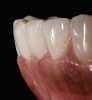

The clinical application of this protocol is illustrated in a patient situation where laminate veneers were placed on four maxillary incisors to replace lost tooth structure and restore function and esthetics. The failing restorations were removed, followed by a conservative veneer preparation (Figure 1 and Figure 2). The bonding surfaces of the feldspathic porcelain veneers were acid-etched with hydrofluoric acid for 2 minutes (Figure 3) and thoroughly rinsed. Then a silane coupling agent was applied (Figure 4). Figure 5 demonstrates the situation after bonding the veneers to the teeth with a composite resin luting agent.

Fig. 2  Preparations for laminate veneers.

Figure 2

Fig. 3  Porcelain veneers were acid-etched with hydrofluoric acid for 2 minutes.

Figure 3